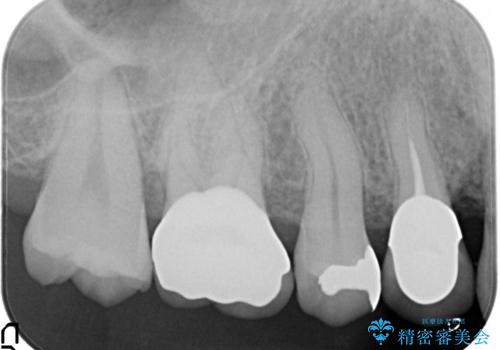

セラミッククラウンによるむし歯治療

- 他院で入れたセラミックインレーがかけたことを主訴に来院されました。

他の部位にもむし歯を認めたため、優先度の高い歯から治療を行っております。

咬合力が強くかかる部分には欠けるリスクのほとんどない金属を用いることが最良ですが審美性に劣ります。

今回は白い材料での修復を希望されたため、欠けるリスクが高いセラミックインレーは避け、セラミッククラウンにて治療を行いました。